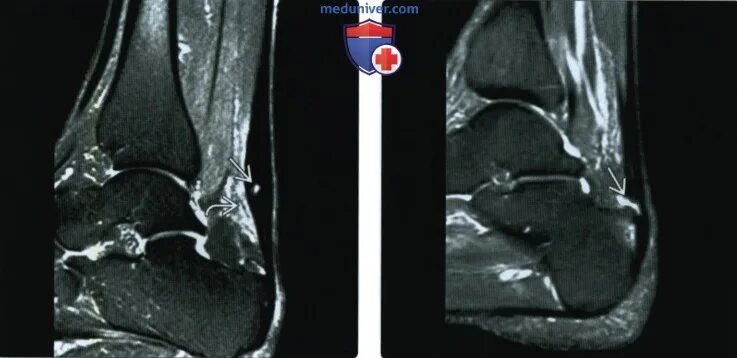

Мрт ахиллового сухожилия